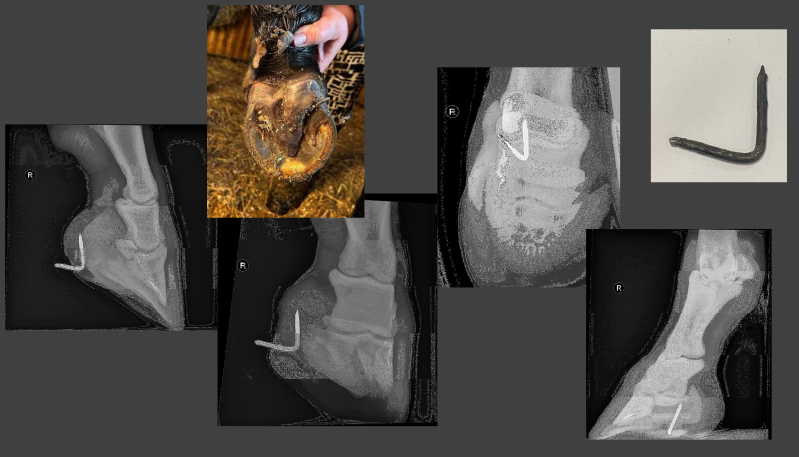

When you have a traumatic nail in hoof situation, what should you not do?

Do not remove the nail immediately, because you will not be able to find the track without the nail in place.

Risk of deep digital flexor tendon and navicular bursa perforation and infection. Navicular bone can lyse due to the inflammation. This would be really bad.

In these images, the nail is only in the digital fat pad which has a better prognosis.

NB tetanus vax! If vax given > 6 months ago, give booster.